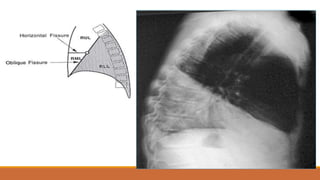

nghiêng

Nguyên tắc:

nghiêng bên nào

bên đó gần phim

Nhận biết: đa số trường hợp

phim nghiêng (P) có 2 vòm

hoành song song với nhau,

phim nghiêng (T) 2 vòm

hoành cắt nhau. Ngoại lệ:

dựa vào các xương sườn

Thế nghiêng: Đạt yêu cầu

1. Thấy toàn bộ phổi từ đỉnh tới góc sườn hoành

2. Cánh tay không chồng lên phế trường

3. Xương ức không bị xoay

4. Các xương sườn hai bên chồng nhau

5. Thấy mạch máu ở khoảng sáng sau tim

Các thùy phổi